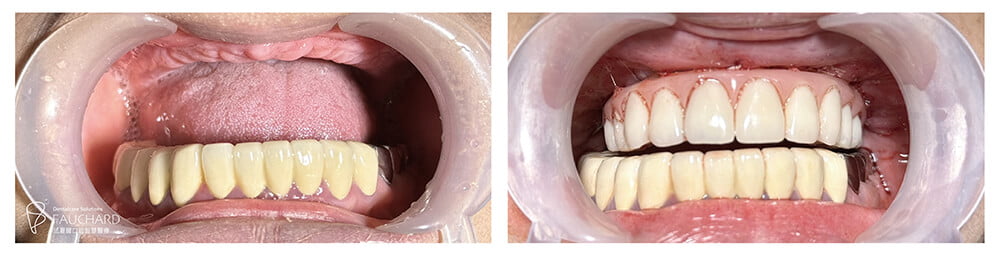

全口重建案例.手術完成|術後驗收 治療成效禁得起考驗

「做好手術,X光一拍,這次骨粉補得滿滿的!」手術當天,盤大哥在旁見證盤太太的手術成果,經過這次療程,盤太太齒槽變得扎實堅固,穩穩地支撐起牙齒。

「吃飯都很順,水果什麼硬的都吃!」全口重建成功案例-盤太太對治療成效感到相當滿意,驚訝地說只有剛完成手術頭幾天牙齦稍微腫痛,從頭到尾都很順,食物樣樣都可吃,最近她還到越南旅遊,終於感受到享受美食的幸福,「真的吃得很開心!」「對啊,我本來擔心她不能咬,要幫她折斷龍蝦腳,沒想到她直接啃了起來,好像大鋼牙!」盤先生在旁吐槽道。